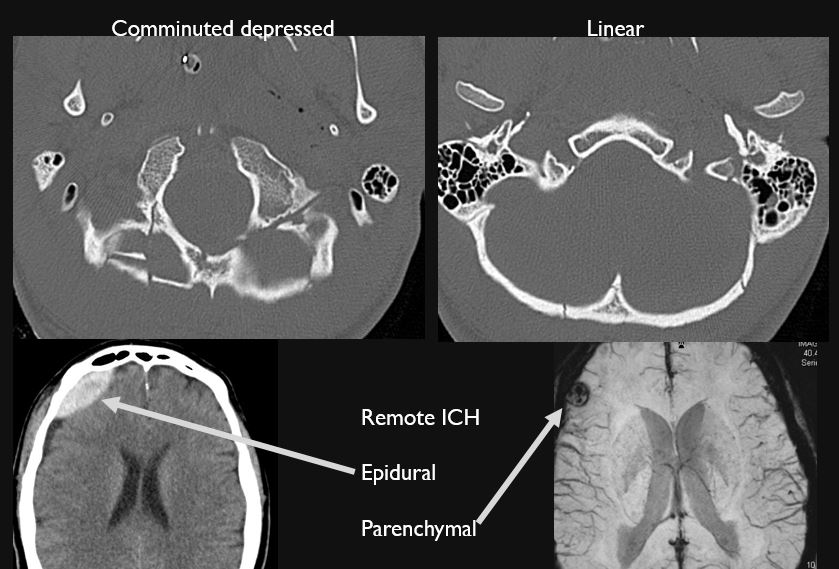

Intracranial and Calvarium

There is evidence of extracranial gas or a foreign body at a possible fracture site.

There is a calvarial fracture.

There is subperiosteal, epidural or subdural hematoma and/or pneumocephalus along the boney walls of the anterior, middle or posterior cranial fossa or elsewhere.